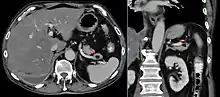

In research, cranial height or brain imaging may be used to determine intracranial volume more accurately.[3]